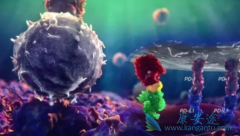

短时间、小剂量的激素,并不会影响 PD-1 抑制剂的疗效。因此,当患者使用PD-1抗体后出现皮疹、间质性肺炎等免疫性炎症反应的时候,使用一定的激素处理这些副作用,是不会影响疗效的,可以放心使用。但是,对于一些需要长期使用激素的患者,尤其是那些每 ...

派姆单抗 (Keytruda)是一种PD-1抑制剂,可以增强人的免疫系统来对抗癌细胞对身体的破坏。尽管派姆单抗在非小细胞肺癌中具有显着的抗肿瘤活性,但与EGFR野生型患者相比,派姆单抗在EGFR突变患者中的治疗效果却不是太好。那派姆单抗治疗EGFR突变,且PD- ...